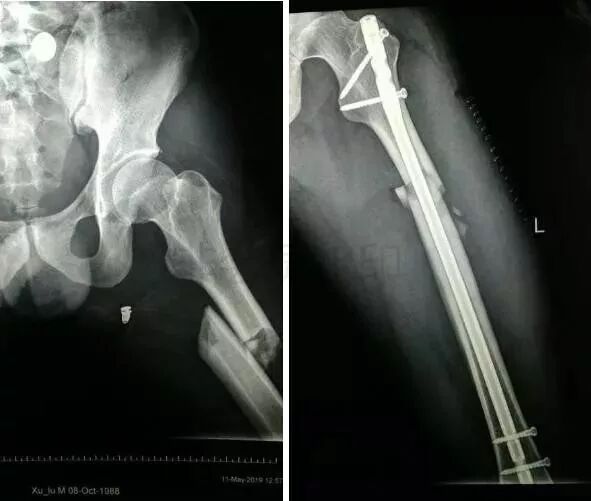

2)股骨干骨折

图片

• 可以急诊做,也可以根据情况限期做。

• 多发伤,髓内钉,可能发生脂肪栓塞-肺栓。